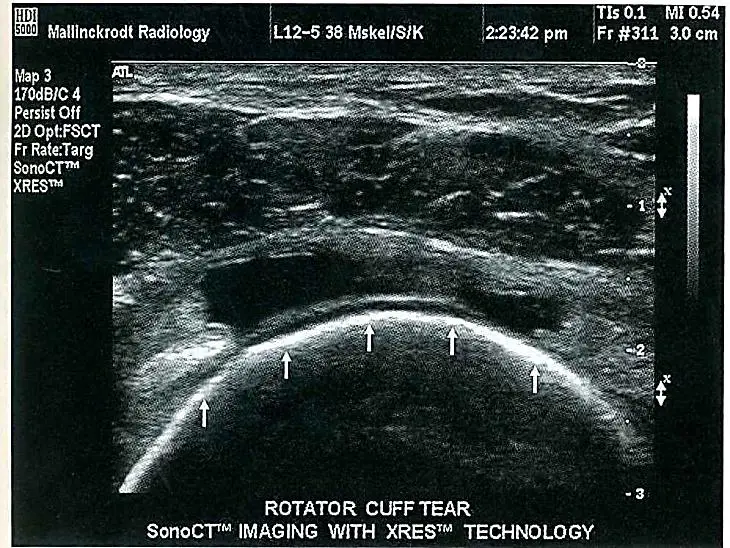

下圖為一超音波影像,下列何者為導致假影(箭頭處)的主要原因?

本題圖片為一張肌肉骨骼系統超音波影像(musculoskeletal ultrasound),可見到組織層次結構。影像中箭頭所指之處呈現典型的顆粒狀斑點紋路(granular speckle pattern),此為超音波影像特有的假影現象。

此種假影表現為整體影像上均勻分布的細小隨機顆粒,並非真實的解剖結構,而是由超音波束與組織內無數微小散射體(scatterers)交互作用後,回傳至探頭的背向散射訊號相互發生建設性與破壞性干涉(constructive and destructive interference)所形成的。這種假影被稱為 speckle artifact,在所有 B-mode 超音波影像中普遍存在。